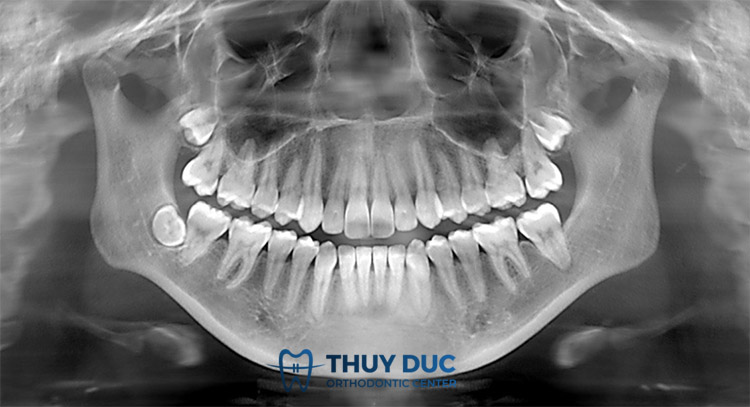

Chụp X-quang răng thực chất là kỹ thuật chẩn đoán hình ảnh giúp theo dõi cụ thể, chính xác nhất tình trạng khoang miệng, phát hiện bất thường răng, xương hàm hay mô mềm. Từ hình ảnh thu được trên phim chụp X-quang, bác sĩ có thể phát hiện những khoang hở, cấu trúc răng ẩn như răng khôn, sâu răng hay cả khối u. Ngoài ra, kỹ thuật này phản ánh hình ảnh rõ nét nhất về chân răng và tủy, từ đó theo dõi cả quá trình điều trị nha khoa.

– Xác định chính xác hình thái, hướng mọc lệch của các răng để xử lý các vấn đề về khớp cắn và thẩm mỹ của bệnh nhân.

– Chẩn đoán sớm, xác định mức độ nghiêm trọng của các vấn đề về răng, nướu như sâu răng, viêm tủy, viêm lợi,… Từ đó đưa ra phương án điều trị kịp thời, tránh các biến chứng về sau.

– Dễ dàng quan sát được các chi tiết nằm sâu dưới chân răng như mạch máu nhỏ quanh răng, ống dây thần kinh. Điều này giúp ích cho quá trình nhổ răng diễn ra an toàn, hạn chế tối đa các biến chứng.

– Phát hiện sớm các tổn thương vùng xương hàm như u, nang, viêm nhiễm hay trong chấn thương.

– Xác định được mật độ xương hàm một cách chính xác nhất.

– Theo dõi cụ thể quá trình mọc răng vĩnh viễn ở trẻ nhỏ.